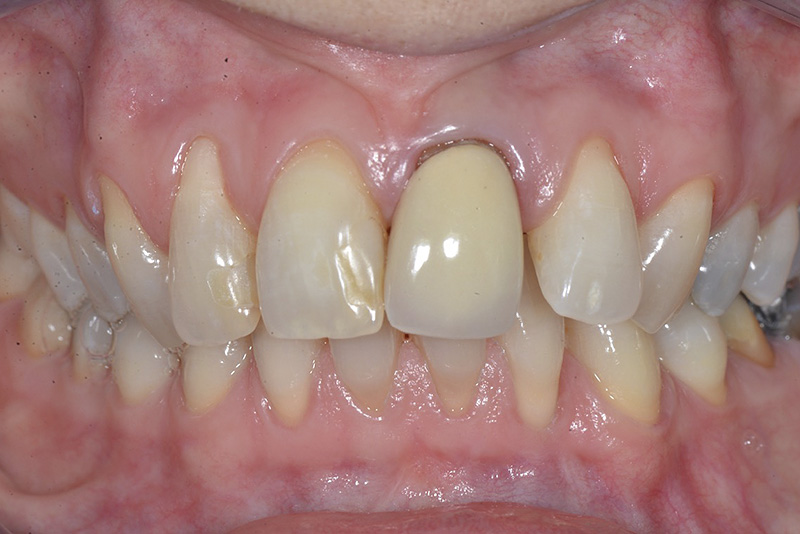

PREMESSA: in seguito all’estrazione dell’incisivo laterale superiore di destra, resasi necessaria per cause batteriche, si decide di affrontare il caso con il posizionamento di un impianto in sostituzione dell’elemento mancante dopo guarigione del sito infetto. Con tecniche rigenerative sia dei tessuti ossei mancanti a causa dell’infezione pregressa, sia dei tessuti gengivali che appaiono inizialmente troppo spostati in alto, si ripristina una corretta morfologia delle parabole (contorni) gengivali e delle papille interdentali (triangoli di gengiva tra due denti vicini).

Vengono utilizzati 2 tipi di provvisori: il primo, cementato ai denti vicini, viene utilizzato dal momento dell’estrazione del dente fino ad impianto osteointegrato (circa 6 mesi); il secondo, avvitato direttamente all’impianto, ha una funzione di prova estetica ma soprattutto di guida per la maturazione dei tessuti gengivali peri-implantari portandoli verso la maturazione completa prima di posizionare la corona finale in disilicato di litio.